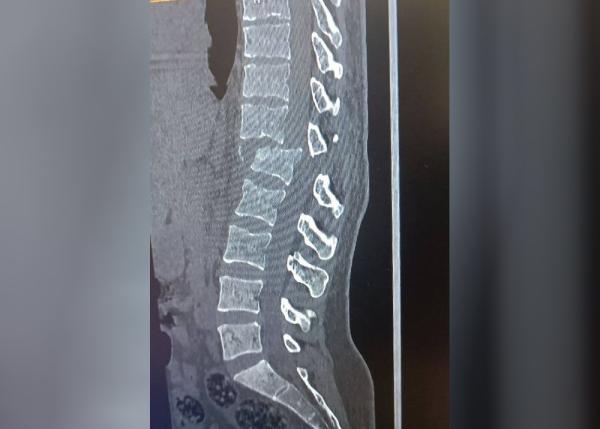

Напомним, в результате наезда у женщины сломан позвоночник, она парализована и находится в больнице. На подозреваемого, который ранее уже был судим, открыли уголовное дело по части 1 статьи 266 (нарушение правил безопасности движения или эксплуатации транспортных средств). По ней предусмотрен штраф до 50 БРВ с лишением определенного права до трех лет. Максимальное наказание – три года тюрьмы.

Позднее судмедэкспертиза показала и другие тяжелые травмы у потерпевшей – сотрясение мозга, переломы ребра и позвонка, гематому, сдавливающую спинной мозг, а также другие повреждения, опасные для жизни.